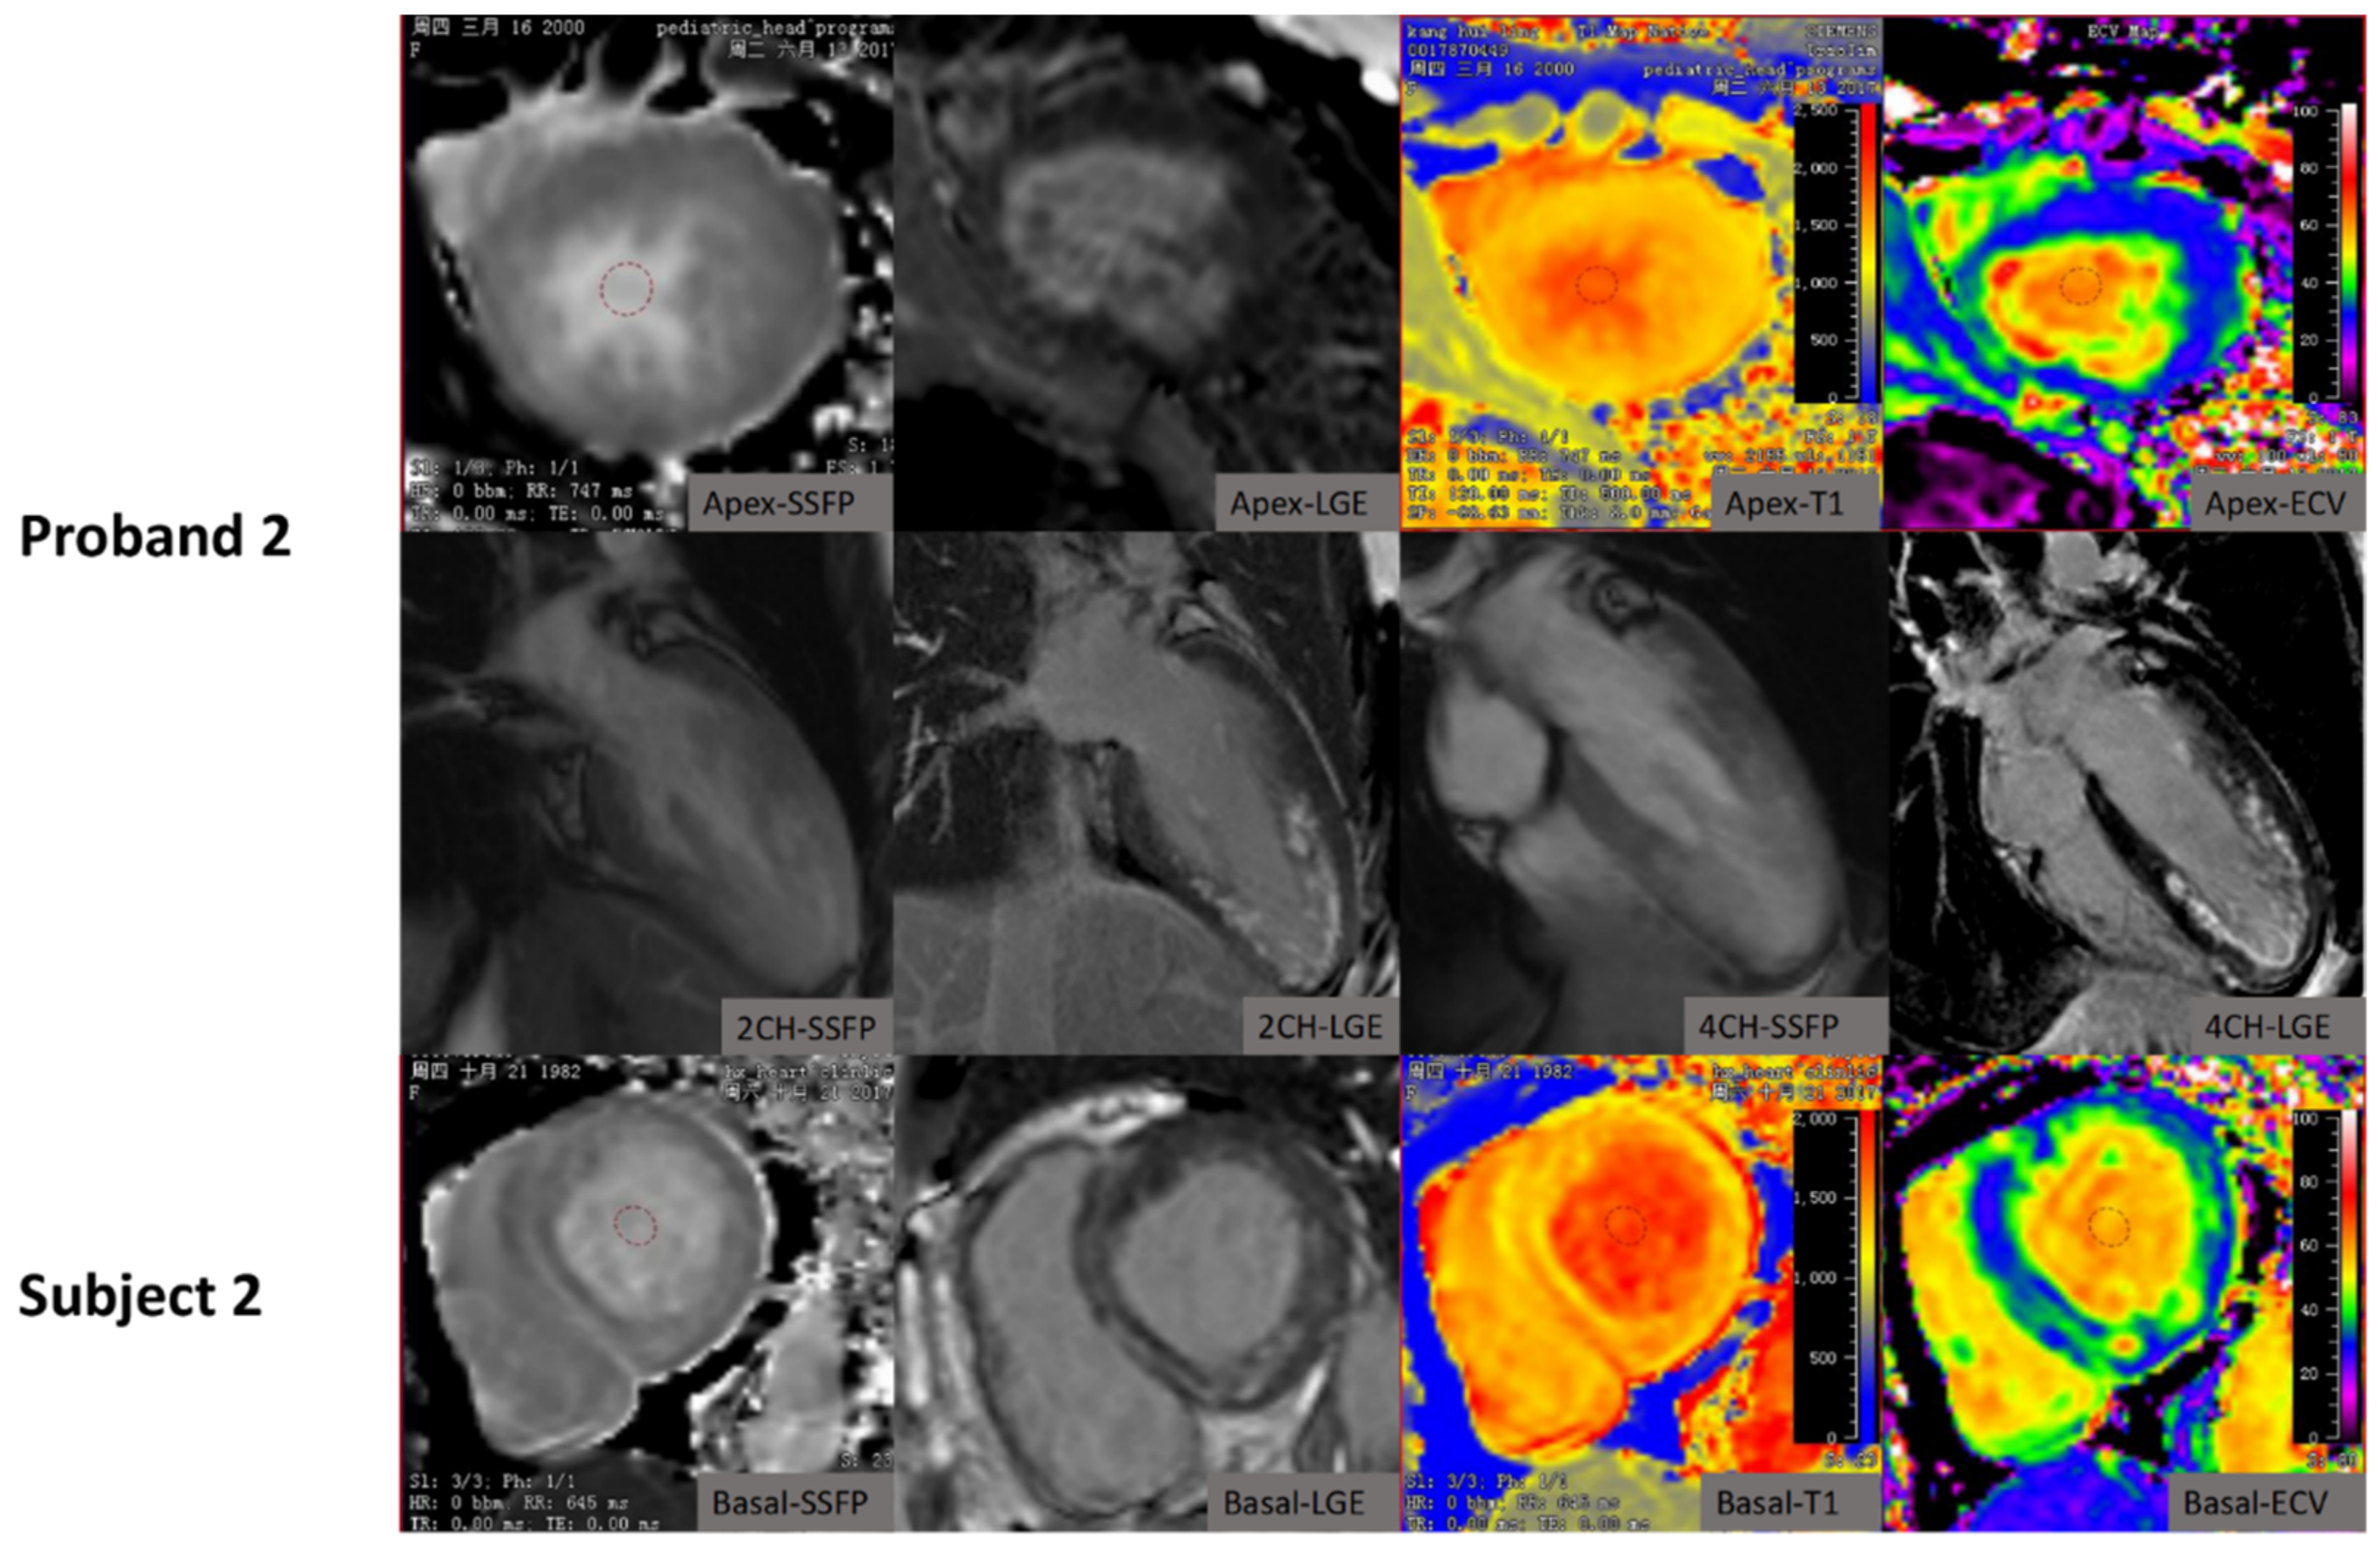

| Proband 1 | LAMP2 (c.64 + 1G > A) | 20 | M | 18.0 | Palpitation, DOE | II | Yes | NSR; ventricular preexcitation; NSST-T | 59.8 | 50.4 | 42 | 33.4 | Extensive fibrosis mainly in mid-myocardium of lateral wall with septal sparing | 1376.5 | 35.5 | ICD implantation; awaiting heart transplantation |

| Subject 1 | LAMP2 (c.64 + 1G > A) | 44 | F | 23.4 | DOE; edema | II | No | NSR; Short PR intervals; PVC | 16.9 | 27.8 | 16 | 18.9 | Non-ischemic sub-endocardial LGE mainly in lateral wall and transmural LGE pattern | 1581.2 | 43.9 | Heart failure managed; awaiting heart transplantation |

| Proband 2 | LAMP2 (c.973delC, p.L325Wfs*21) | 17 | F | 20.0 | Syncope, | I | Yes | NSR;ST-T | 65.7 | 69.4 | 15 | 14.7 | Patchy circumferential non-ischemic sub-endocardial LGE | 1392.1 | 31.6 | ICD implantation recommendation |

| Subject 2 | LAMP2 (c.973delC, p.L325Wfs*21) | 42 | F | 18.8 | DOE | II | No | NSR; NSST-T | 64.0 | 55.9 | 14 | 23.4 | Multiple focal LGE area in whole wall | 1318.7 | 37.8 | Heart failure managed |